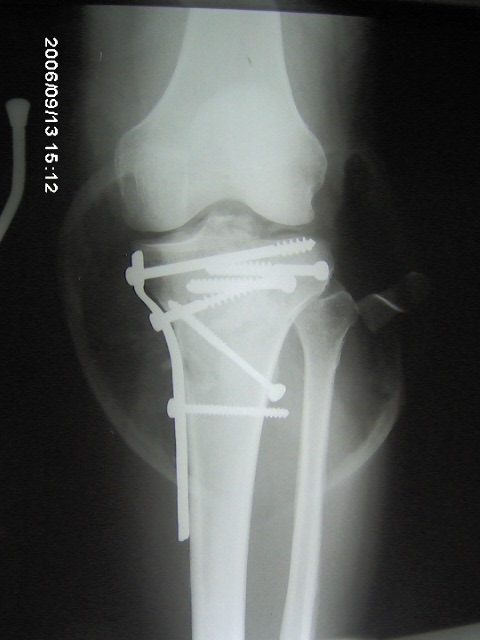

Fracturas ver más

Reparación de fracturas. Atencion dependiendo de la gravedad, quirúrgica o no quirúrgica